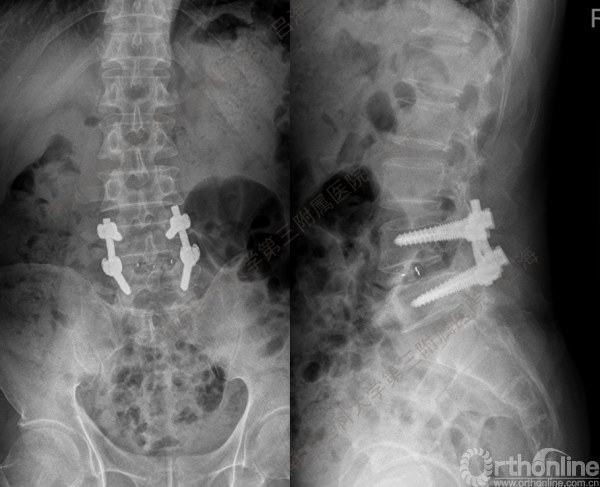

随着社会老龄化进程加快,胸腰椎退行性病变的治疗已经成为脊柱学术界的一个热点话题。MIS-TLIF手术可以治疗多种不同的胸腰椎退行性疾病,南方医科大学第三附属医院吕海教授结合病例为我们一一展示了该术式在治疗不同胸腰椎疾病时的具体手术过程。